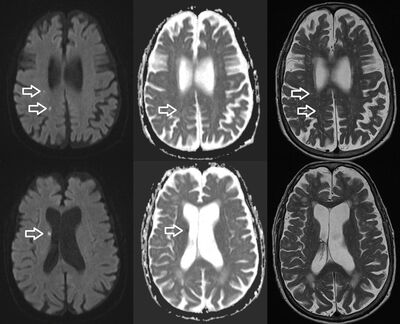

Einkenni komu aðeins fram þegar hún var á fótum, versn-uðu við áreynslu, til dæmis í handlegg þegar hún lyfti honum upp yfir axlarhæð. Hún var einkennalaus í hvíld (sitjandi eða liggjandi). Ofhreyfingarnar lýstu sér eins og grófur skjálfti í handlegg og fótlegg. Í handleggnum kom skjálftinn aðallega fram í framhandlegg og hendi og líktist hvorki hvíldarskjálfta í Parkinsonveiki, ættlægum skjálfta (essential tremor) né reglukenndum kippum eins og í staðflogi. Samhliða þessum ofhreyfingum varð hún dofin í vinstri hendi og fann ekki fyrir því sem hún hélt á og átti það til að missa hluti vegna þessa. Ekki var máttminnkun til staðar. Engin skerðing varð á meðvitund í köstunum sem flest voru mjög áþekk. Vegna þessara einkenna var hún nánast hætt að hreyfa sig, sat eða lá að mestu fyrir. Tölvusneiðmynd (TS) af heila hafði sýnt ósértækar lágþéttnibreytingar á grunni smáæðasjúkdóms, ekki sáust merki um blóðþurrð eða blæðingu. Konan fór í segulómun (MRI) af heila- og hálsmænu. MRI sýndi fjölda smærri blóðþurrðarbreytinga í hægra heilahveli (mynd 1).

Mynd 1. Segulómun af höfði sýnir litlar segulskærar breytingar í hægra heilahveli á B1000 myndum (örvar í fyrsta dálki) sem að hluta til eru sýnilegar á T2-vigtuðum myndum (örvar í þriðja dálki) en bara nokkrar eru með lágu segulskini á ADC-korti (örvar í öðrum dálki) eins og við skert flæði (diffusionsskerðingu). Þetta útlit bendir til blóðþurrðarbreytinga af mismunandi aldri.